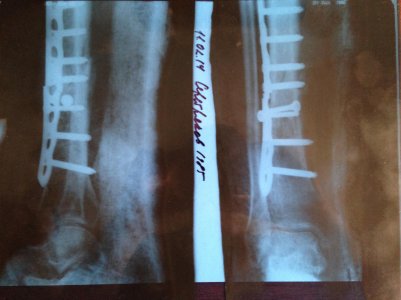

Здравствуйте.24.04.2013 получил перелом :Закрытый винтообразный перелом на уровне н/3 б/б. в/3 м/б костей правой голени со смещением отломков.Врач не сказал какая пластина установлена. ИЗ ВЫПИСКИ:названии операции:ОТКРЫТАЯ РЕПОЗИЦИЯ ПЕРЕЛОМА ОСТЕОСИНТЕЗ ПЛАСТИНОЙ.Вопрос Какую пластину мне поставили и нужно операционно удалять.Если да.Через сколько?

Здравствуйте, сломал ногу берцовую кость 14092013, вот мучаюсь 8 месяц. С момента операции прошло 2 месяца, начал наступать на ногу сломал и пластину, боли пошли. Приехал к врачу сделали снимок, наложили гипс циркулярный, прошло еще 4 месяца. Вот снимок сказали переходи на палочку, 3 недели ходил появилась боль, опухла. Поехал к врачу он сказал лангета еще на два месяца, сейчас в лангете осколки некоторые упали вниз к мазоли, другие заросли, сам перелом треснул из-за того что рано начал разрабатывать. В лангете хрусты небольшие и немного играет кость, третьего снимка щас нету, в больнице. Как ДУМАЕТЕ зарастет или нет? Что делать? СПАСИБО ЖДУ ОТВЕТА.

IMG_0803.jpg

IMG_0806.jpg